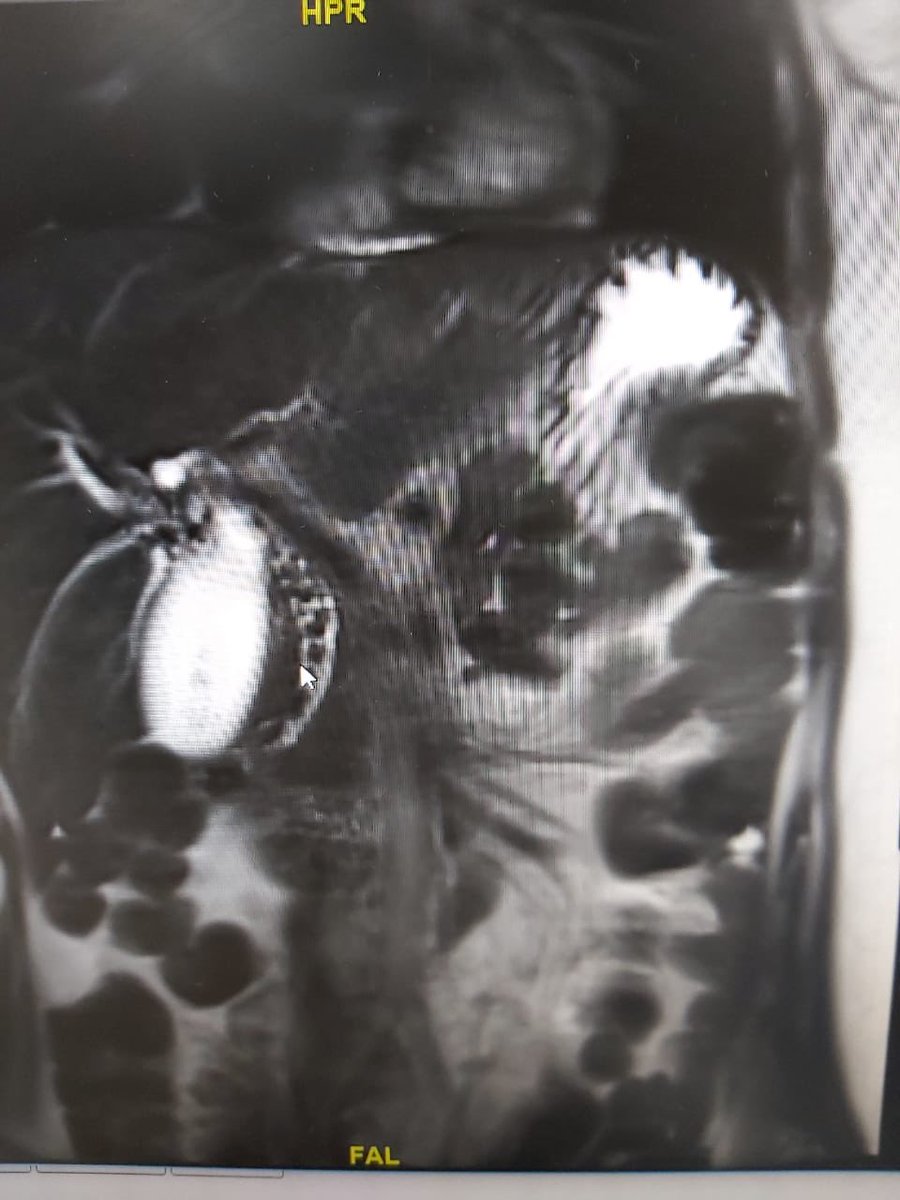

والأشعة المسموحة هي رنين مغناطيسي

كيس القنوات المراريه👇في حجم اكبر من البرتقالة